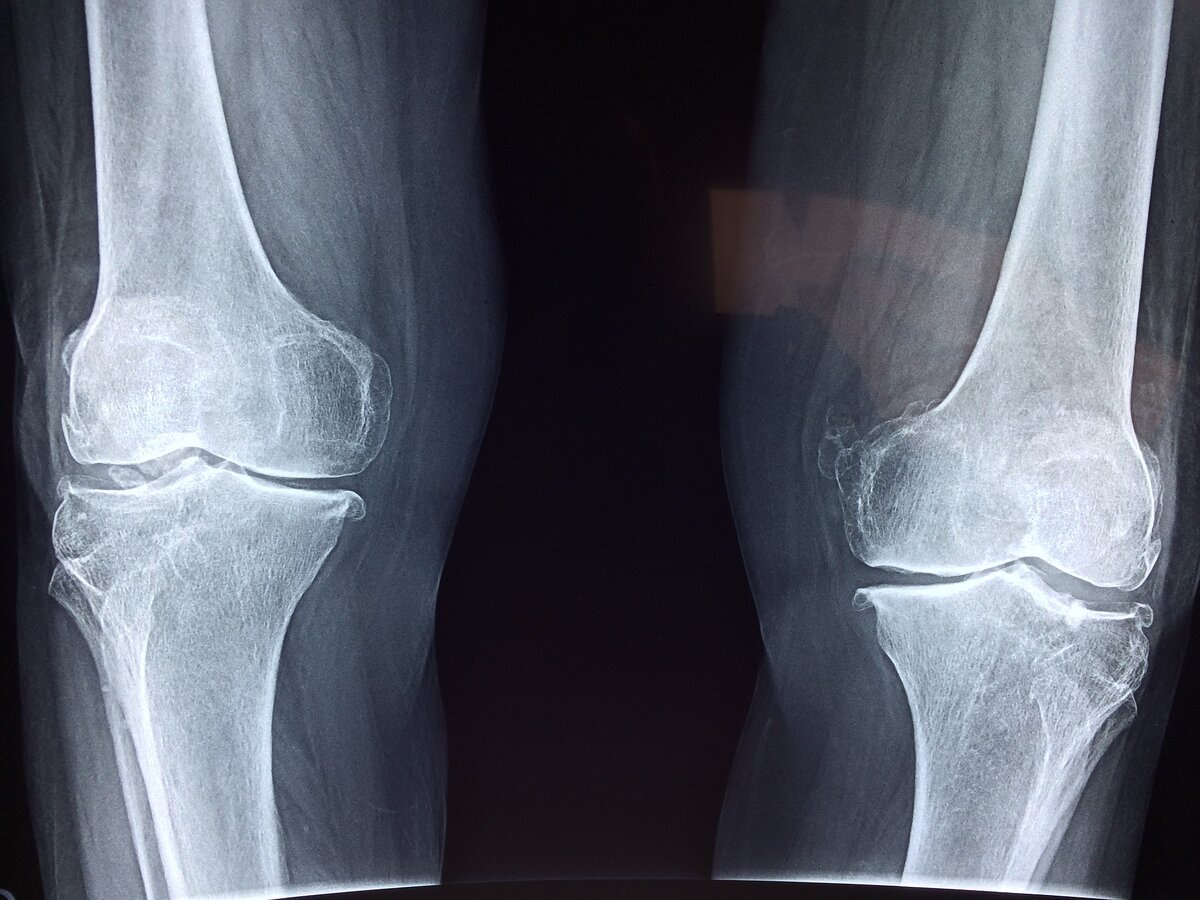

Хруст в коленях – причины и лечение

Хруст в коленях, причины и как избавиться от этого — вопрос, интересующих многих. В человеческом организме, казалось бы, все продумано для полной свободы передвижения: десятки суставов и сочленений, мышцы. Конечности свободно сгибаются-разгибаются, амортизируют. Но в то же время возникает и множество заболеваний опорно-двигательного аппарата. От чего так? Например, человеческие колени ежедневно испытывают колоссальную нагрузку, хоть их строение и предназначено для этого, но из-за неправильного распределения нагрузки и ряда других причин, сложная система коленного сустава начинает давать сбой. Болевой синдром, припухлость, часто хруст. Именно о хрусте в коленях сегодня пойдет речь: откуда он берется, опасно ли данное явление и есть ли способы от него избавиться. Основными причинами патологического хруста в коленях медицина считает: 1. Разрушение хрящевой ткани в силу возрастных изменений в организме или по причине наличия хронических заболеваний. 2. Частое ношение модельной, как прави

Основными причинами патологического хруста в коленях медицина считает:

1. Разрушение хрящевой ткани в силу возрастных изменений в организме или по причине наличия хронических заболеваний.

12. Поражения коленных суставов артрозом, артритом и другими болезнями воспалительного характера.